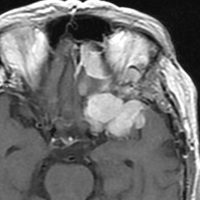

左は,造影剤を使ったガドリニウム増強MRIです。腫瘍が白く丸く見えます。右はフレア画像で,腫瘍の周囲の脳浮腫(脳のはれ)です。左前頭葉が,かなり強くはれています。この腫瘍は小さいのですが,脳のはれが強すぎるので手術摘出したほうがいいです。浮腫が悪化すると,てんかん発作や認知機能低下がでる可能性があります。